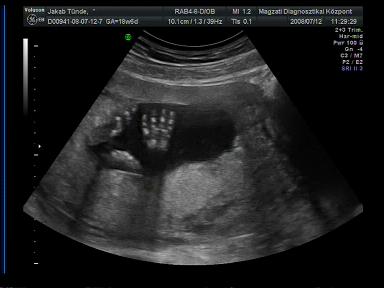

Jók a pocifotók!

Szeretnék segítséget kérni fizetős genetikai UH ügyben: ki hol járt és mennyire volt megelégedve a szolgáltatással? Ja, és a legfontosabb, hányadik hétig lehet menni ilyen genetikai UH-ra???

Ugyanis ma voltam a kórházban UH-n és kb. 3 perc alatt lerendeztek. A doki közlékeny volt, de nagyon rohamtempóban történt minden. Szóval hogy megnyugodjak teljesen, szeretnék elmenni egy alaposabb vizsgálatra is. A nemének beazonosításában is nagyon készséges volt doki bácsi, de Pötty szégyenlős volt (lehet, ez már utal valamire

) és jól összezárta a lábait. Amúgy az ő vizsgálatuk szerint minden ok. És medence végű, ami nem tudom, hogy jót jelent-e, mindenesetre a doki ezzel magyarázta, hogy nem tud sokat mocorogni, mert nincs túl sok helye ott.